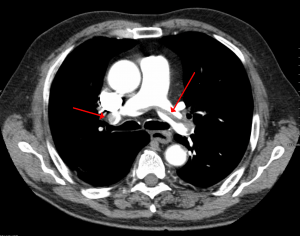

A large pulmonary embolism at the bifurcation of the pulmonary artery (saddle embolism).

Definitive Diagnostic Imaging